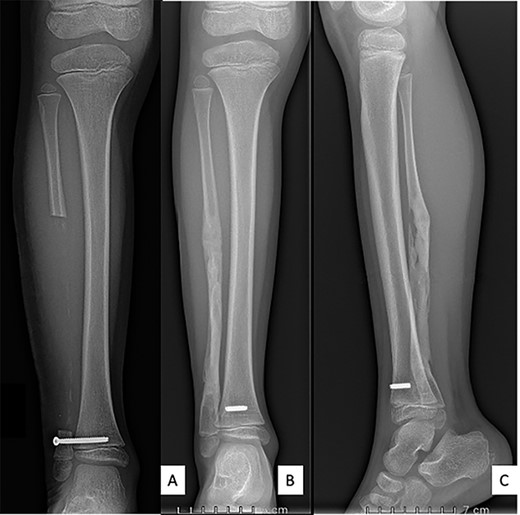

Ultrasound showed a diaphyseal subperiosteal hematoma of the fibula with cortical irregularities. The radiograph showed a pathological fracture, at the upper end of a cortical bone lesion of mixed osteolytic and osteoformative character with bone callus (Fig. 1). MRI showed a multifocal osteolytic cortical process extending along the fibular shaft, without tumor mass in the soft tissues with respect for the signal of the medullary cavity. The perilesional soft tissues were respected, but they appeared in strong hypersignal T2 and enhanced after injection of gadolinium (local inflammatory reaction or post-traumatic changes; Fig. 2).

Anteroposterior (A) and lateral (B) radiographs of right fibula showing pathological fracture on a cortical bone lesion of mixed osteolytic and osteoformative character with bone callus.